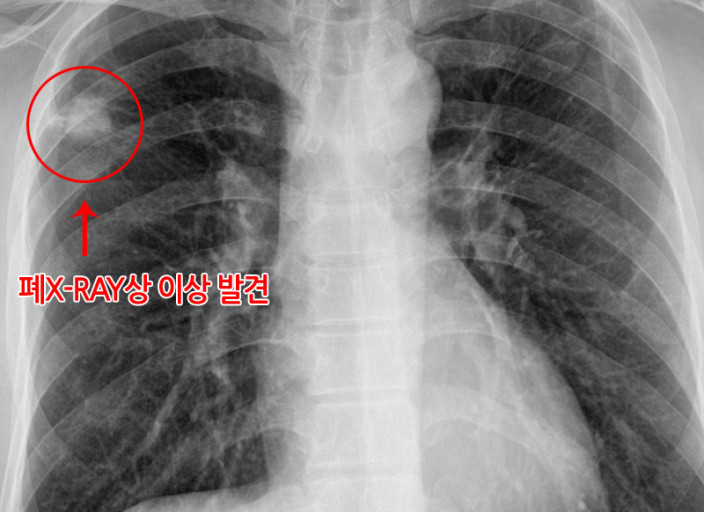

폐암은 위암, 갑상선암 다음으로 3번째로 발병 빈도가 높은 3대 암 중 한 가지인데요. 폐암은 재발과 전이까지의 빈도도 잦은지라 완치가 어렵다고 하며 폐암 발병 초기에는 거의 증상이 없을 수가 있어 수술이 불가능한 3기, 혹은 4기에 주로 진단된다고 해요.

폐암 초기증상 폐암 4기에 이르게 되면 5년 생존률이 30% 대로 감소하게 된다고 해요. 그리하여 폐암은 암 질병이자 중 사망자 비율이 가장 높은 것으로 나타나고 있어요.

폐암은 사망률 2위를 차지하고 있는 간암에 비해 무려 2배에 가까운 사망률을 보이고 있다고 합니다. 이렇게 치명적인 폐암에 대해 미리 알고 대처하는 것이 바람직할 것 같아요. 아래에서는 폐암이라 판단해 볼 수 있는 그 초기증상에 대해 간단히 설명드릴게요.